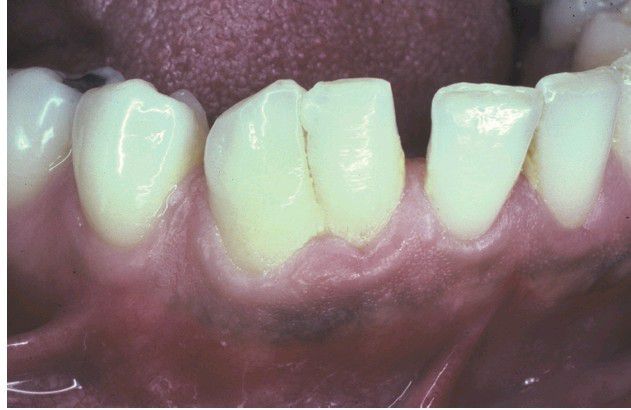

Double tooth in the place of the mandibular right lateral incisor and cuspid

Fusion